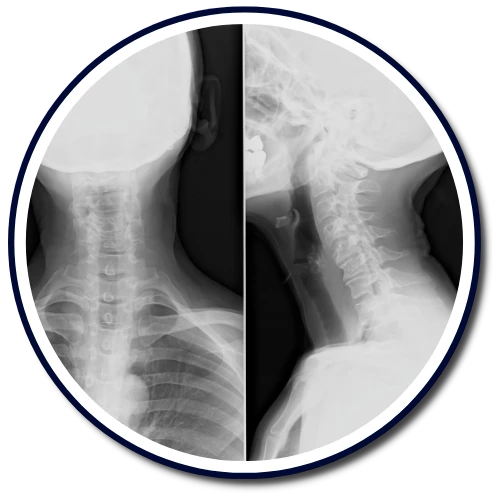

The Gonstead Technique relies on five essential components: Visualization, Instrumentation, Palpation, X-Ray, and patient symptoms. By integrating these elements, we can pinpoint the precise location that requires adjustment. When all these factors align, we can provide the patient with a specific and effective adjustment. Specificity is the key, as Dr. Gonstead emphasized that three adjustments on the wrong vertebral segment could lead to a Subluxation, highlighting the importance of precision.

Dr. Gonstead's Level Disc Theory asserts that "anatomically and physiologically normal discs promote optimum vertebral alignment." This is evidenced when the vertical height of a vertebral couple is uniform around 360 degrees, with the vertebral bodies properly aligned. This alignment, known as "Parallel Discs," ensures even weight distribution, adequate nutrient flow, and optimal joint function and movement within the spine.